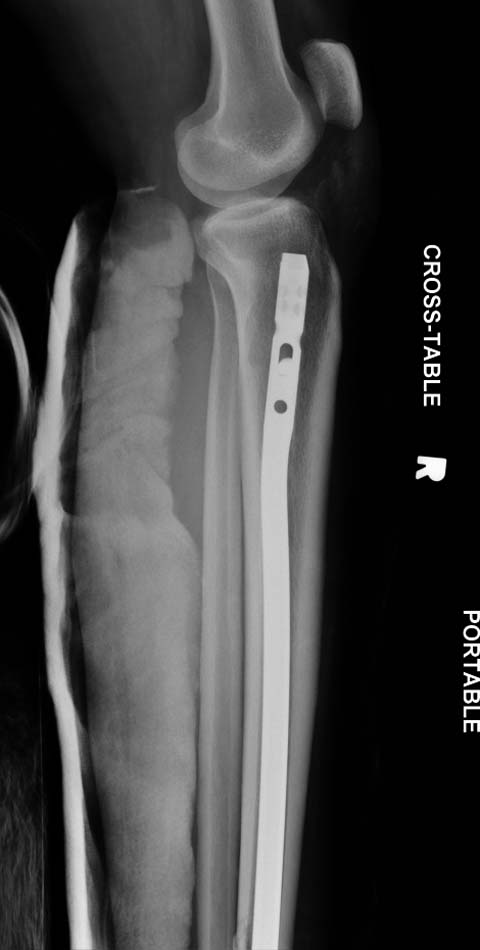

Гвоздь сильно коротковат, есть ощущение, что проксимальный блокирующий винт мимо гвоздя, ну и варус - не вальгус, конечно...

"проксимальный блокирующий винт мимо гвоздя"

дистальный, конечно же - тот, что попроксимальнее из 2х дистальных)

Хотя, по существу, гвоздь действительно короткий, и не смотря на это, заблокирован дистально только одним винтом - не стабильно

Не смотря на пойлерный винт остается варусное смещение дистального отломка и ротация его.

1. Гвоздь ОЧЕНЬ коротковат. Нет репозиции большеберецовой, гвоздь в дистальном отломке пошел по задней стенке.

Разбор любого случая кому-то поможет лучше ориентироваться в решении вопросов, потому что в нашей работе встречаются разные связанные и несвязанные с мастерством хирурга ситуации. Возможно, отсутствие полного набора гвоздей повлияло на выбор короткого имплантата, имеется угловая и ротационная деформации. Независимо от локализации, стабильность создается, когда гвоздь проксимально не глубже 1.5 см (облегчает удаление) и дистально доходит до epiphyseal scar.

Мнение о том, что гвоздь сделает репозицию не всегда соответствует истине. Снимки показывают на неудачную попытку исправить направление гвоздя с помощью “поллеров”. Прием возможен только тогда, когда проход риминга в центре канала, иначе толкать гвоздь некуда.